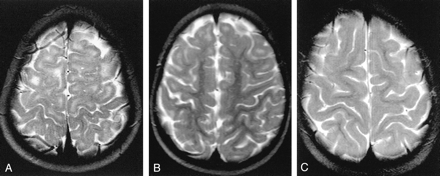

Axial T2-weighted MR images.

A, Image in a 21-month-old girl with grade 0 myelination in the frontal lobe. The subcortical white matter is clearly hyperintense, so not myelinated, in the prerolandic area and along the first and second convolutions bilaterally. Subcortical hyperintensity was also evident in the frontopolar regions.

B, Example of grade 2 myelination in the frontal area. A T2 hyperintensity is present along the first and second convolutions, while the prerolandic area is myelinated.

C, Example of grade 3 myelination. T2 hyperintensity is no longer evident, and myelination appears complete.